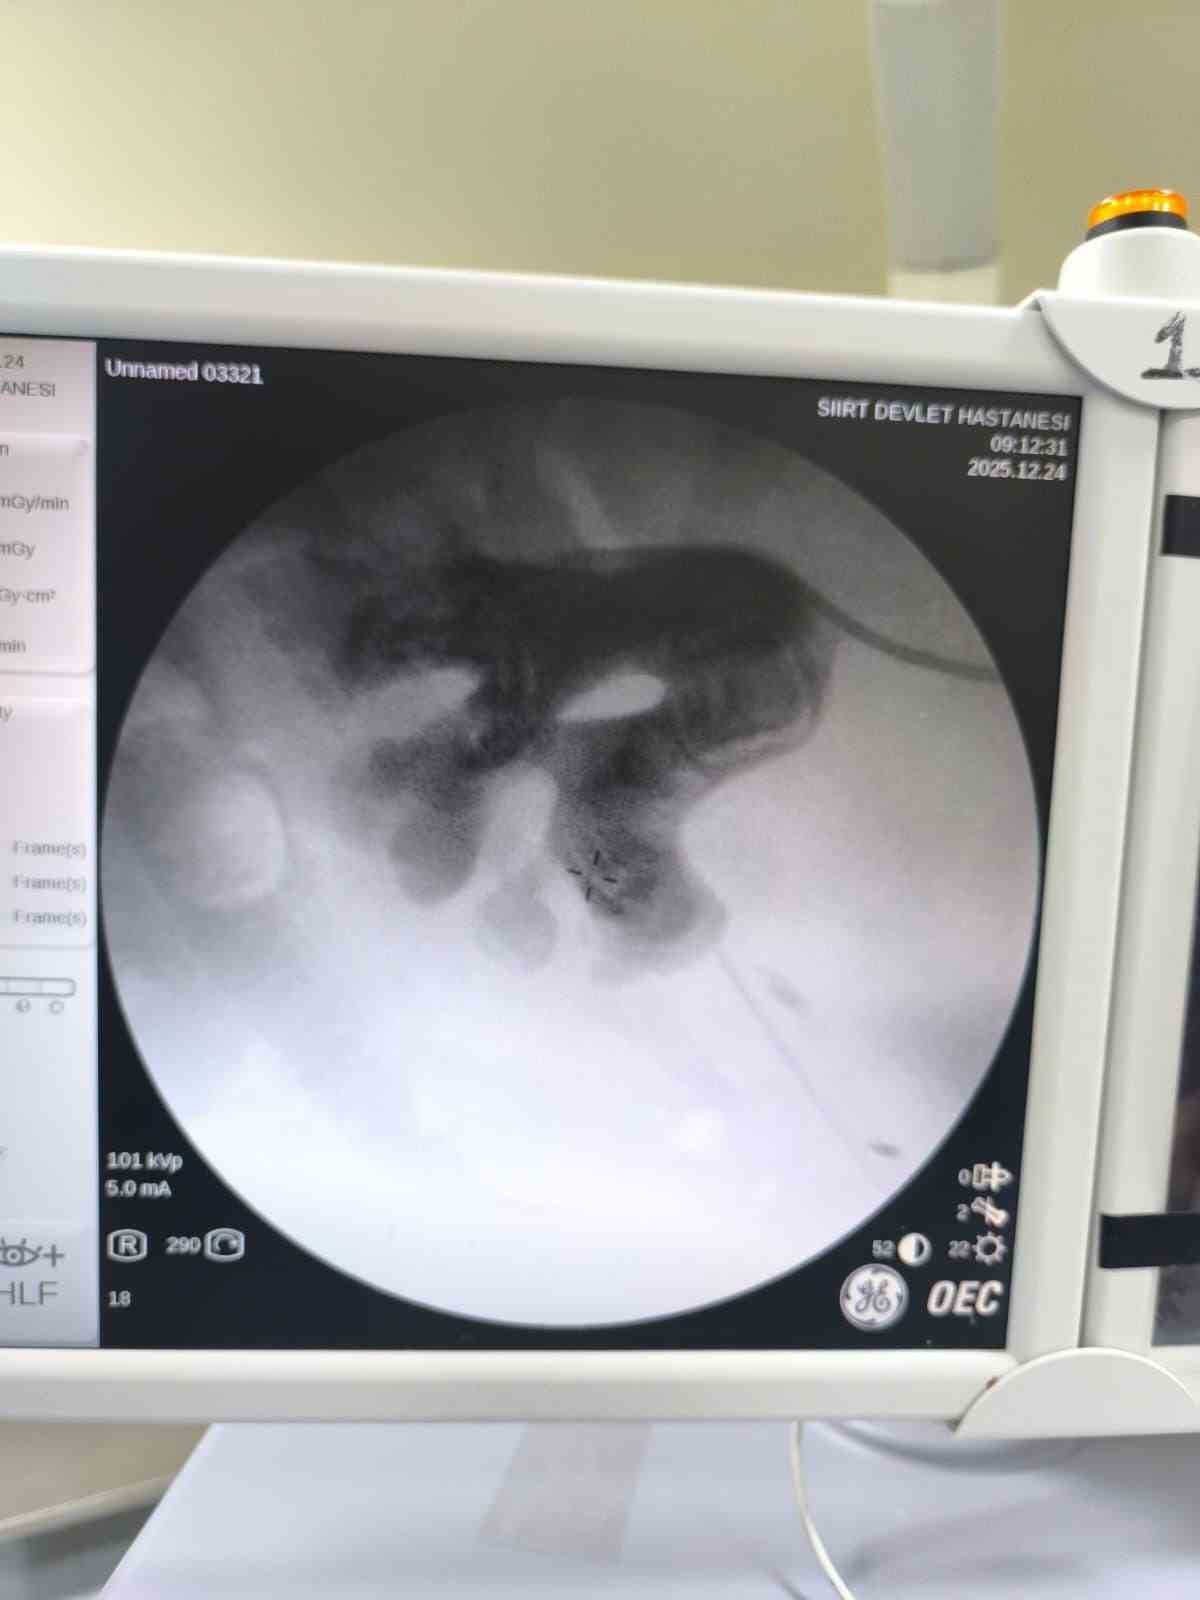

Siirt’te 34 yaşındaki Fatih Aslan, ateş, üşüme ve idrar yaparken yanma şikayetleriyle hastaneye başvurdu. Yapılan muayene ve testlerin ardından piyelonefrit (böbrek iltihabı) tanısı konuldu ve enfeksiyon tedavisi tamamlandı. Üroloji uzmanı doktor Miraç Ataman, gerçekleştirilen operasyon, hem tıbbi açıdan hem de toplumsal sağlık açısından önemli bir başarı olduğunu söyledi. Ataman, “34 yaşındaki erkek hastamız, ateş, üşüme ve idrar yaparken yanma şikayetleri ile acil servise başvurdu. Yapılan değerlendirme sonucunda piyelonefrit (böbrek iltihabı) tanısı konuldu ve yatış yapılarak enfeksiyon tedavisi başarıyla tamamlandı. Tanı sürecinde yapılan Bilgisayarlı Tomografi (BT) görüntülemesinde böbreğin tamamını kaplayan, sert yapıda(950-1450 HU), literatürde staghorn olarak adlandırılan ve halk arasında ‘ geyik boynuzu taşı ’ diye bilinen büyük taş saptandı. Staghorn taşlar böbreğin tüm boşluklarını doldurup, tekrarlayan enfeksiyonlara ve uzun vadede böbrek fonksiyon kaybına yol açabildiğinden tedavisi hayati önem taşımaktadır. Biz de bu vakamızda, Perkütan Nefrolitotomi (PCNL) yöntemiyle böbreğe küçük bir cilt kesisi üzerinden girerek endoskopik cihazlarla taşları parçalayıp çıkardık. PCNL, özellikle çapı 2 cm’den büyük ve kompleks taşlarda altın standart kabul edilmektedir. Normalde staghorn taşların temizlenmesi uzun süren ve çoğu zaman birden fazla seans gerektiren zorlu bir süreçtir. Modern altyapısı sayesinde, ciltten tek giriş yolu açılarak yaklaşık 1,5 saatlik bir seansta böbreğin tüm taş yükü başarıyla temizlendi” dedi.